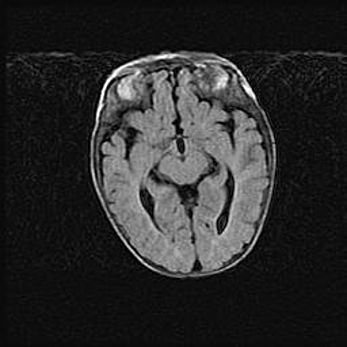

Сообщающаяся гидроцефалия. Кистозная энцефаломаляция головного мозга.

Возраст: 3 месяца 4 дня

Вес: 3100 г

Пол: женский

Окружность головы: 34 см

Срок гестации: 31 неделя

Кистозная энцефаломаляция головного мозга - одна из форм поражения головного мозга в детском возрасте. Характеризуется возникновением множественных и распространённых кист в коре, белом веществе и подкорковых образованиях головного мозга у плодов, новорождённых и детей раннего возраста. Развитие кистозной энцефаломаляции связано с внутриутробной асфиксией и гипотонией, родовой травмой, тромбозом синусов, пороками развития сосудов, инфекциями, сепсисом и другими причинами. Наиболее значимые инфекционные агенты: вирусы простого герпеса, цитомегалии, краснухи, токсоплазмы, энтеробактерии, золотистый стафилококк и другие.